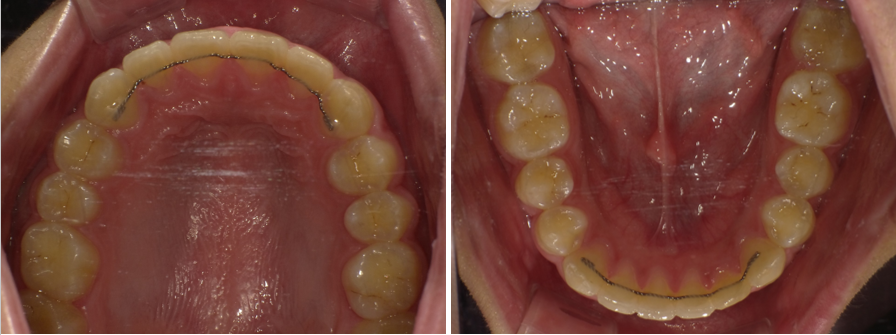

7f829c6152fc0f266ad641c0f7ec26e1_1763089992_2853.png

판교교정치과 / 견인 중인 매복치

느렸지만, 끝내 올라온 매복치

매복치의 맹출 속도는 예상보다 더디었습니다.

치아의 위치가 깊었고, 아이의 협조도 문제도 있었기 때문이죠.

하지만 꾸준히 견인을 유지하며 아이의 협조를 격려했고,

결국 매복된 하악측절치가 잇몸 위로 자연스럽게 올라왔습니다.

구강 내로 올라온 치아에 브라켓 장치를 부착하여 치아배열을 시행했습니다.

7f829c6152fc0f266ad641c0f7ec26e1_1763090060_0868.png

7f829c6152fc0f266ad641c0f7ec26e1_1763090060_1712.png

판교교정치과 / 치료 후 구내사진